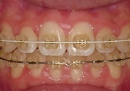

☆審美ワイヤー(光拡散型)の使用例と

ホワイトワイヤー(コーティング)での治療例

審美ホワイトワイヤー

光拡散ロジウムコートtypeワイヤー

ゴールドシリーズ審美ワイヤー

ホワイトコーティングtypeワイヤー